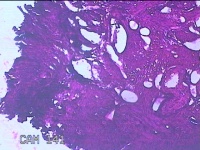

宫腔粘连组织

性别

女

年龄

38岁

临床诊断

1.药流不全 2.宫腔粘连

一般病史

药物流产厚阴道出血10天。

标本名称

大体所见

灰白暗红色不规则碎组织2x1.3x0.8cm一堆。